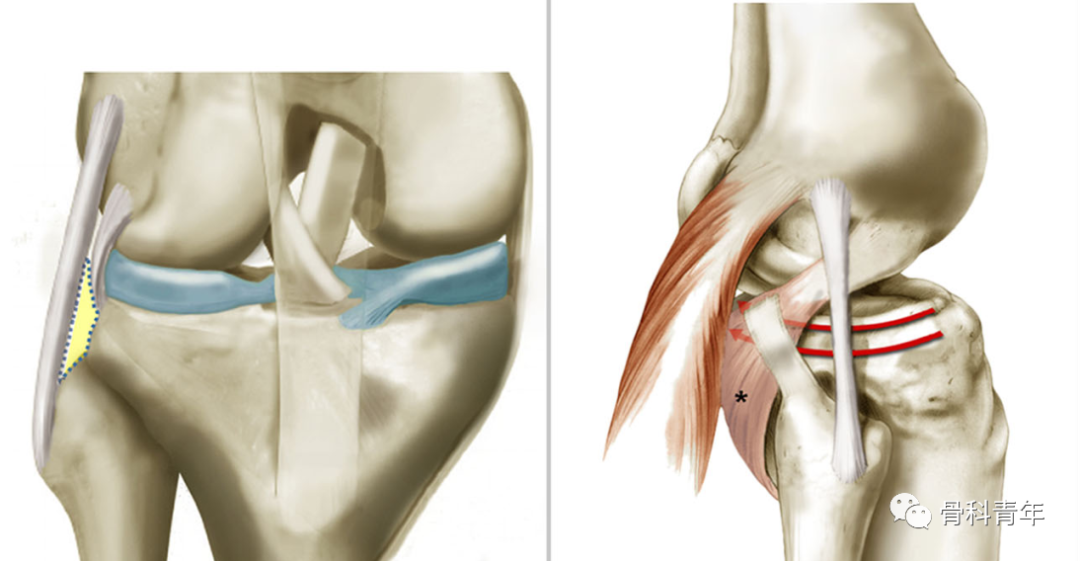

步骤1:患者仰卧位,标准前外侧切口,暴露髂胫束,并将其从Gerdy结节上剥离。切开膝关节外侧关节囊,暴露半月板及外侧副韧带,将半月板缝线固定,掀开半月板即可直视下观察外侧平台骨折及复位情况。松解外侧副韧带与胫骨近端之间的间隙,为防止钢板提供空间。

(LatPlat:胫骨外侧平台;LM:外侧半月板;LCL:外侧副韧带;ITB:髂胫束)

步骤3:常规后内侧切口,在膝关节屈曲20°下,显露腓肠肌内侧头并将其向后牵拉,沿着胫骨后柱骨面边缘松解软组织,预留钢板放置空间。在屈曲状态下可确保膝关节血管神经松弛,上述操作在血管神经束的前方进行。